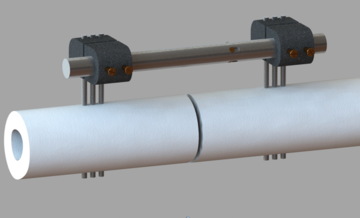

Universal Fracture Healing Accelerator for External Fixators

Medical Devices